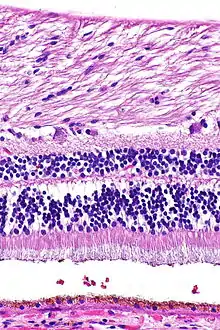

H&E stain

H&E is the combination of two histological stains: hematoxylin and eosin. The hematoxylin stains cell nuclei a purplish blue, and eosin stains the extracellular matrix and cytoplasm pink, with other structures taking on different shades, hues, and combinations of these colors.[5][6] Hence a pathologist can easily differentiate between the nuclear and cytoplasmic parts of a cell, and additionally, the overall patterns of coloration from the stain show the general layout and distribution of cells and provides a general overview of a tissue sample's structure.[7] Thus, pattern recognition, both by expert humans themselves and by software that aids those experts (in digital pathology), provides histologic information.

Hematoxylin principally colors the nuclei of cells blue or dark-purple,[6][15][14] along with a few other tissues, such as keratohyalin granules and calcified material. Eosin stains the cytoplasm and some other structures including extracellular matrix such as collagen[5][7][14] in up to five shades of pink.[8] The eosinophilic (substances that are stained by eosin)[5] structures are generally composed of intracellular or extracellular proteins. The Lewy bodies and Mallory bodies are examples of eosinophilic structures. Most of the cytoplasm is eosinophilic and is rendered pink.[10][15] Red blood cells are stained intensely red.

The structures do not have to be acidic or basic to be called basophilic and eosinophilic; the terminology is based on the affinity of cellular components for the dyes. Other colors, e.g. yellow and brown, can be present in the sample; they are caused by intrinsic pigments such as melanin. Basal laminae need to be stained by PAS stain or some silver stains, if they have to be well visible. Reticular fibers also require silver stain. Hydrophobic structures also tend to remain clear; these are usually rich in fats, e.g. adipocytes, myelin around neuron axons, and Golgi apparatus membranes.